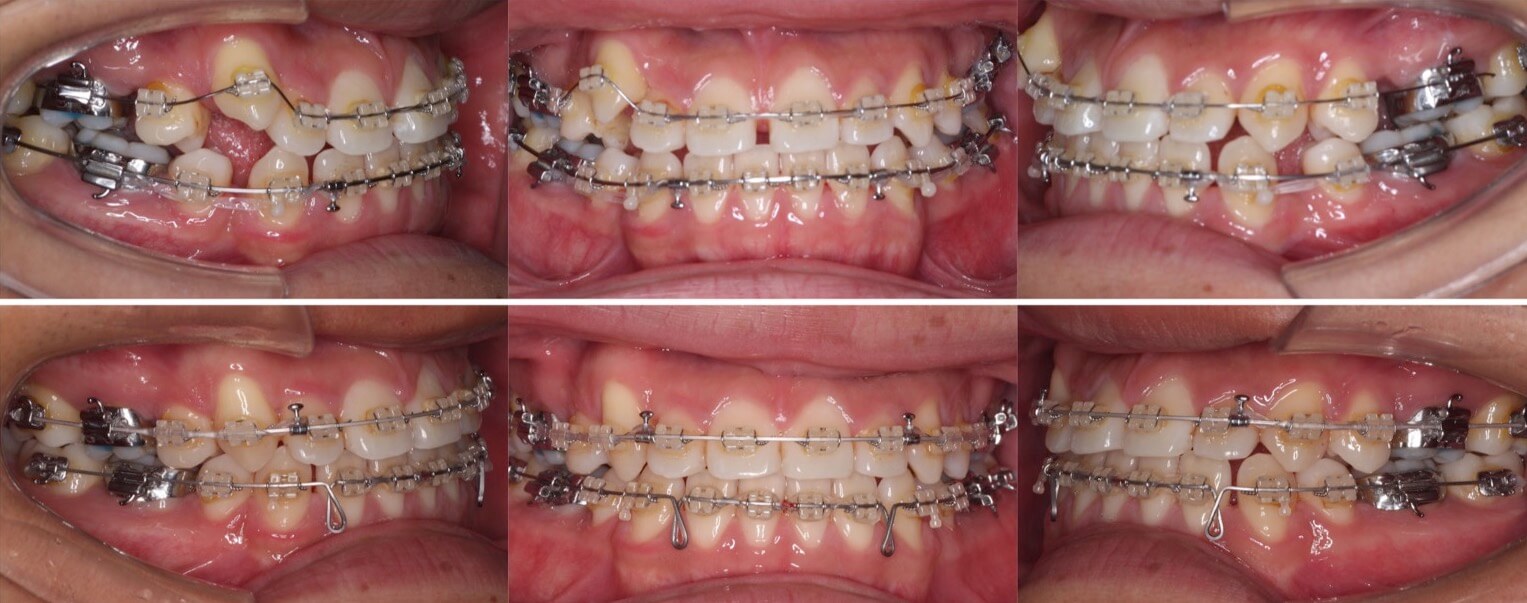

大学生女性・唇側矯正装置・小臼歯4本抜歯

歯が並ぶスペース不足が大きく、前歯の不揃いが強いケースです。また、上下の前歯は開咬状態になっており咀嚼障害もあります。上下小臼歯抜歯を行いできたスペースをうまく利用して前歯を並べ、III級顎間ゴムを使用し下の歯列全体を親知らずを抜歯した後方へ起こしました。非常に難しい治療方針でしたが、ご本人がゴムの使用を頑張ってくれたので予定より早く治療期間も終わり、審美的にも機能的にも良い歯並びになりました。

治療方針:上下小臼歯抜歯・空隙閉鎖

治療装置:唇側矯正装置

固定装置:上バイヘリックス装置・III級顎間ゴム

抜歯:上第二小臼歯・下第一小臼歯・下親知らず(計6本)

治療期間:2年2か月

リテーナー:上下フィックスタイプ+クリアタイプ

治療費用:968,000(税込)

代表的副作用:痛み・治療後の後戻り・歯根吸収・歯髄壊死・歯肉退縮